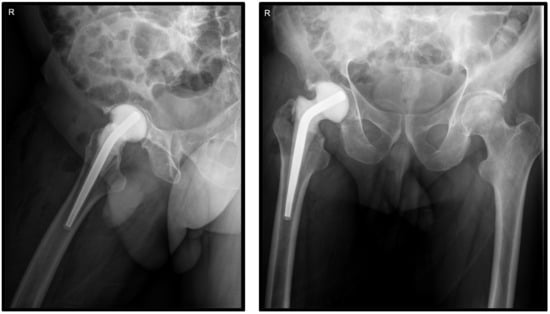

Surgical treatment was planned on the basis of clinical and paraclinical performed investigations and the joint damage. The hip was explored using an anterior approach under spinal anesthesia and standard antibiotic prophylaxis, via an anterior approach. Prior to joint opening, synovial fluid was harvested for microbiological examination. After joint opening, five tissue and bone samples were harvested and sent to the laboratory for bacterial culture. After resection of the femoral head, accurate debridement of all inflammatory tissues was performed, and a preformed temporary spacer (Vancogenx®Space Hip, Tecres S.p.A., Sommacampagna, Verona, Italy) was implanted in the femoral canal (Figure 2). The vancomycin and gentamicin hip spacer (Vancogenx®) was loaded with a 1:1 concentration of antibiotics containing a combined total of 1.1 g to 3.2 g antibiotics.

Figure 2. Postoperative X-ray assessment showing the antibiotic-loaded spacer.